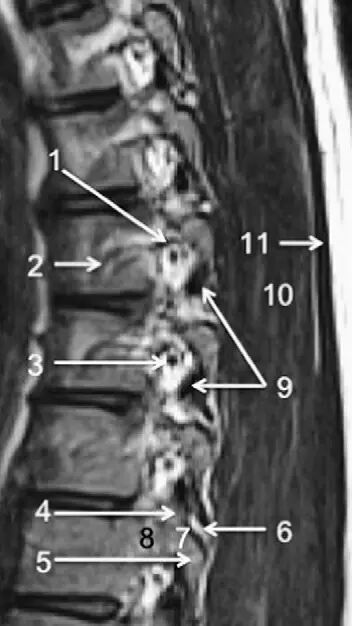

脊柱的MRI解剖

脊柱的韧带

2、前纵韧带:起自枕骨或寰椎前结节,沿椎体的前面向下延伸至骶骨,该韧带下端增宽,与椎体紧密相连,但与椎间盘连结较松。

3、后纵韧带:沿椎体的后面走行,分为浅、深两层。

浅层在枢椎体处与覆膜相连,向下延伸至 L3和L4之间的椎间盘。深层相当于寰椎十字韧带的延续,延伸至骶管。在颈部,浅层较宽,而在胸和腰区变窄,于L3/L4下方与深层愈合。深层在颈部非常薄,而在胸、腰部的椎间盘和椎体上缘的嵴处形成菱形扩展。

前、后纵韧带增加了脊柱的稳固性,这种作用在脊柱的屈、伸运动中尤其明显。因此,它们有两个功能,即限制脊柱运动和保护椎间盘。

4、黄韧带:呈节段性,位于相邻的椎弓之间,构成了椎间孔的后内侧界。由于该韧带主要由呈网格排列的弹性纤维构成,所以呈黄色。这些韧带即使在休息状态也保持紧张。当屈脊柱时,黄韧带伸长,协助脊柱恢复直立姿势。

7、棘间韧带:是连于棘突(D9)之间的短韧带。

8、棘上韧带:起于第7颈椎的棘突,延伸至骶骨,参与构成椎骨与骶骨的连结。